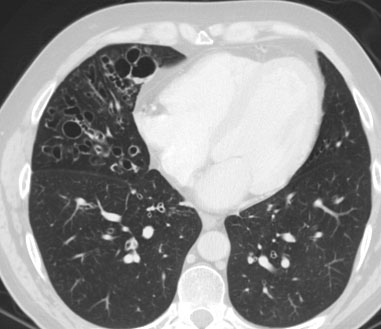

SIGNO DEL RACIMO DE UVASracimoEste signo consiste en el agrupamiento de bronquiectasias quísticas, tal como se ven en el lóbulo medio de este paciente. Este signo también es visible en la radiografía de tórax.